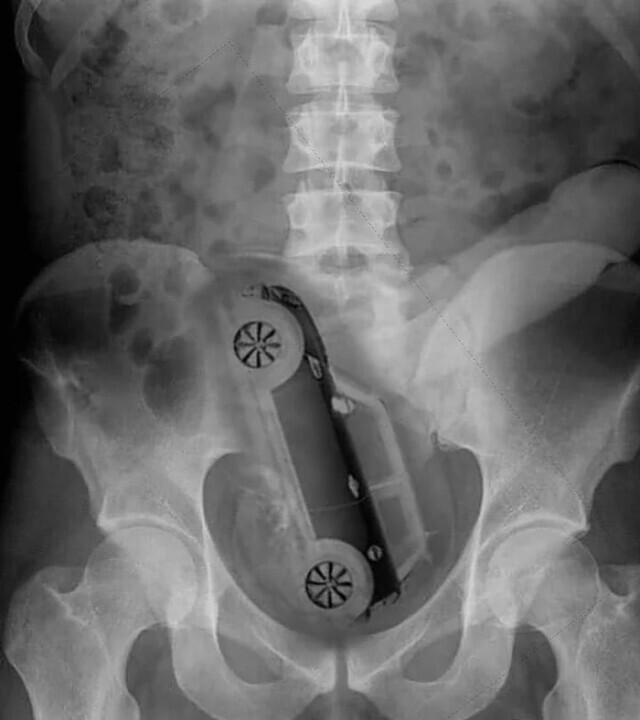

9. Модель машини "Міні Купер"